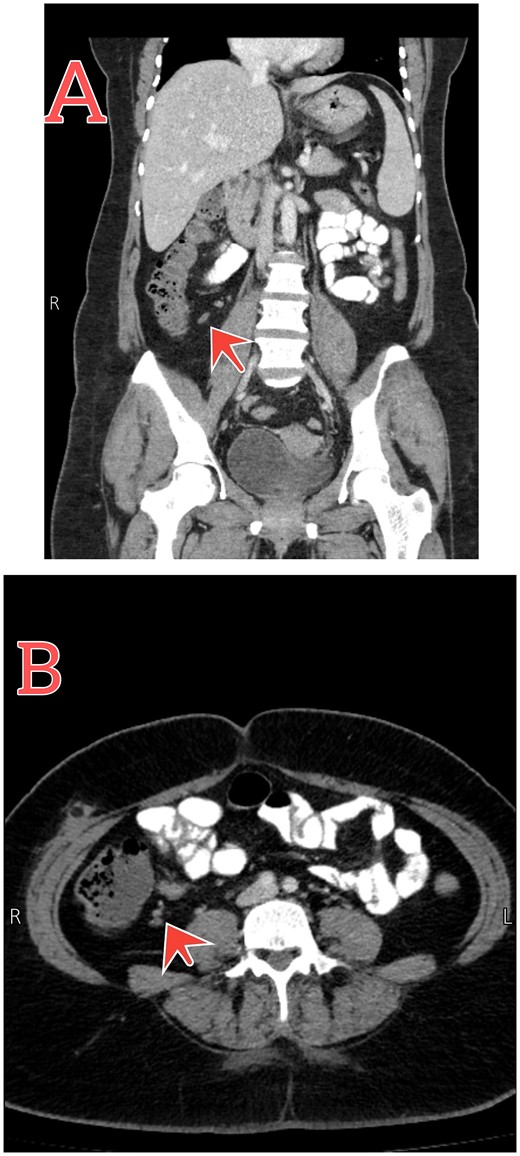

The patient was treated conservatively for two days by giving IV cefuroxime 1.5 mg three times per day, metronidazole 500 mg three times per day, pantoprazole 40 mg once daily, and acetaminophen 1 mg four times per day. Follow-up CT scan showed resolution of the condition (Fig. 2). She was discharged back home with good general conditions without complications.

Follow-up abdomen–pelvic CT scan. (A and B) Coronal and axial sections show resolution of the inflammatory process postconservative management (red arrows).